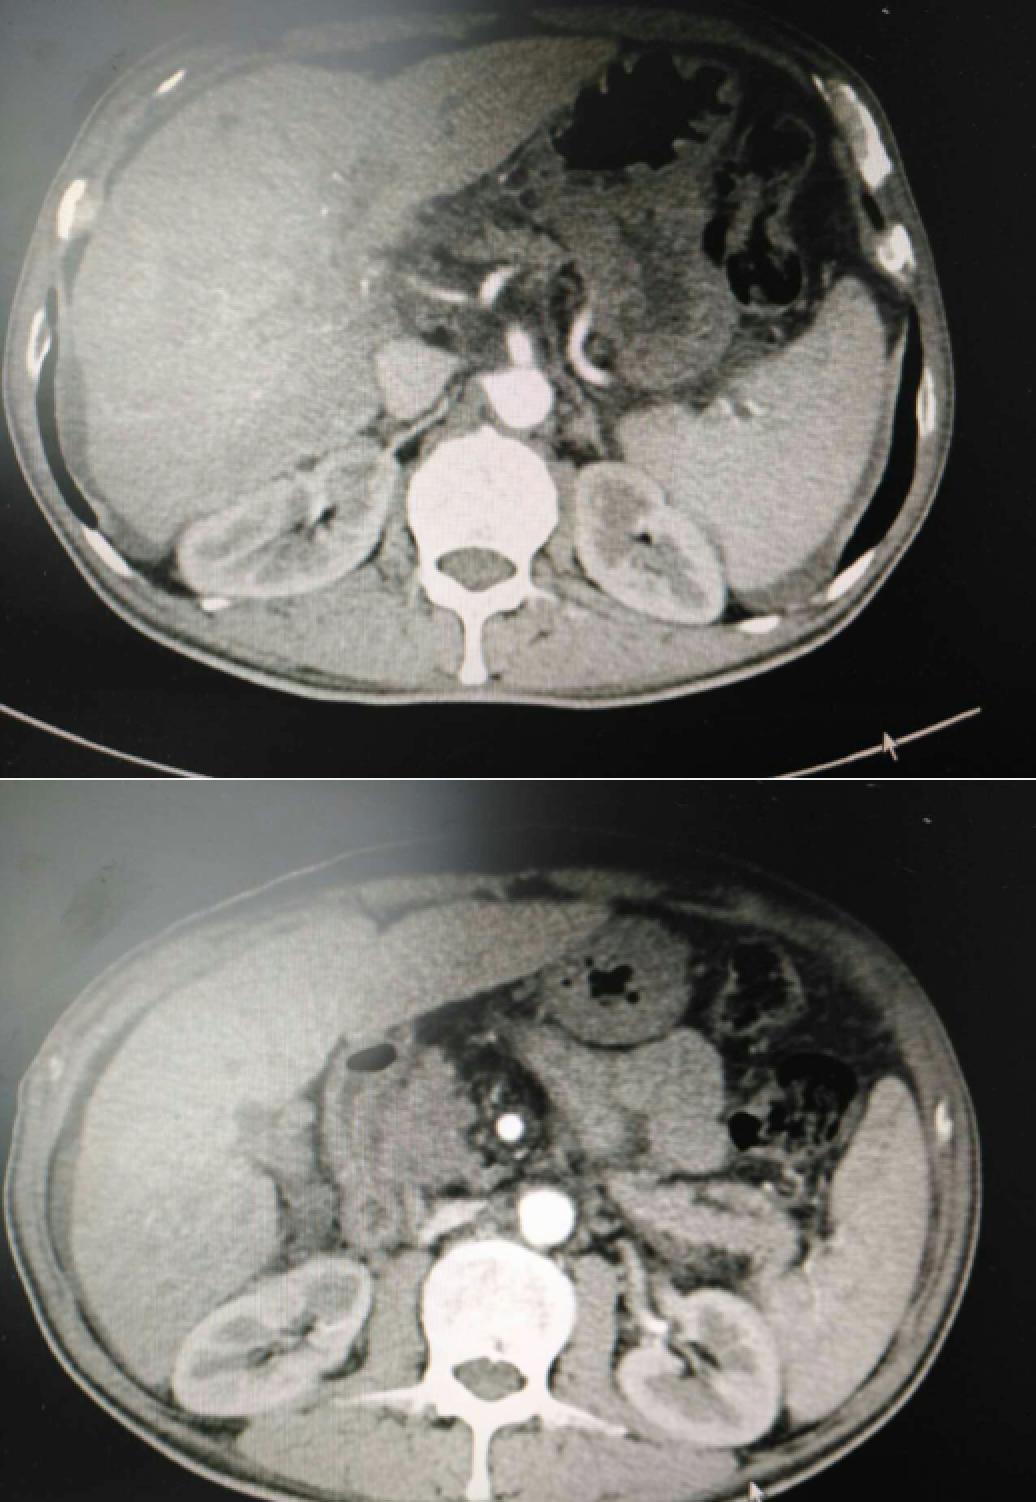

患者因纳差、烧心、腹痛、腹胀2月,于2016-01-17在某县人民医院行腹部CT示肝癌并门脉癌栓形成。分别于2016-01-22、2016-02-19于某市医院行两次TACE术(具体不详)。患者介入术后规律服用抗乙肝病毒、保肝、提高免疫力等药物治疗。2016-02-03至2016-04-30在某省立医院行5周期CIK免疫治疗。2016-05-18至2016-05-25于我院行射波刀治疗门静脉癌栓,具体放疗计划为:42Gy/7F。2016-06-24在我院行肝右动脉化疗栓塞术+肝右动脉灌注化疗术+间接门脉灌注化疗术,术中化疗总量,吡柔比星2mg、顺铂12mg、氟尿嘧啶250mg。分别于2016-05-10、2016-05-27、2016-06-13、2016-07-01、2016-07-27、2016-08-22、2016-09-19、2016-10-07、2016-10-19、2016-11-18、2016-12-18、2017-02-18行12周期免疫治疗。自2016-05-12起患者间断口服靶向药物阿帕替尼250-500mg/d,血压维持在220-130/95-70mmHg,血压升高期间伴上腹部不适,左侧为著,并向腰背部放射,偶尔反酸、烧心,剑突下疼痛,口服抑酸剂或进食后缓解,临床诊断为十二指肠溃疡,目前口服奥美拉唑、马来酸依那普利、氢氯噻嗪等药物对症降压。2017-03-02于我院行第二次肝右动脉化疗栓塞术+肝右动脉灌注化疗术+间接门脉造影术+肠系膜上动脉灌注化疗术。术中化疗总量,洛铂10mg、氟尿嘧啶500mg、吉西他滨400mg。目前间或皮下注射胸腺法新、重组人干扰素α-2b提高免疫力及慢性乙型病毒性肝炎治疗效果。

患者相关影像资料

4. 2017-3-15 DSA造影图中显示肿瘤组织血供一般,也未见癌栓显影,说明肿瘤组织或癌栓血供一般,也可能是靶向药物+栓塞化疗后,主要供血血管已闭塞,继续栓塞治疗效果有限。